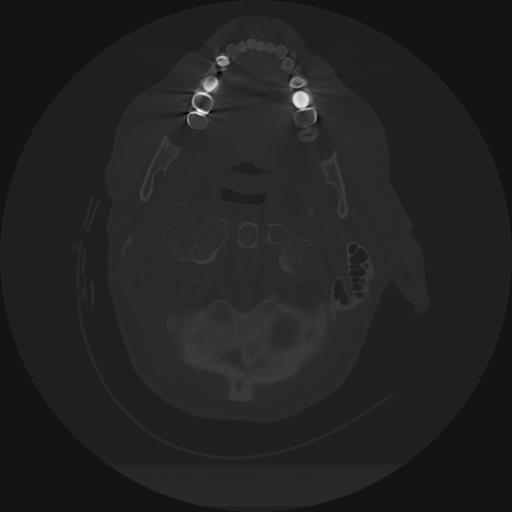

11 HUESO,,Axial,2.0,HUESO,,